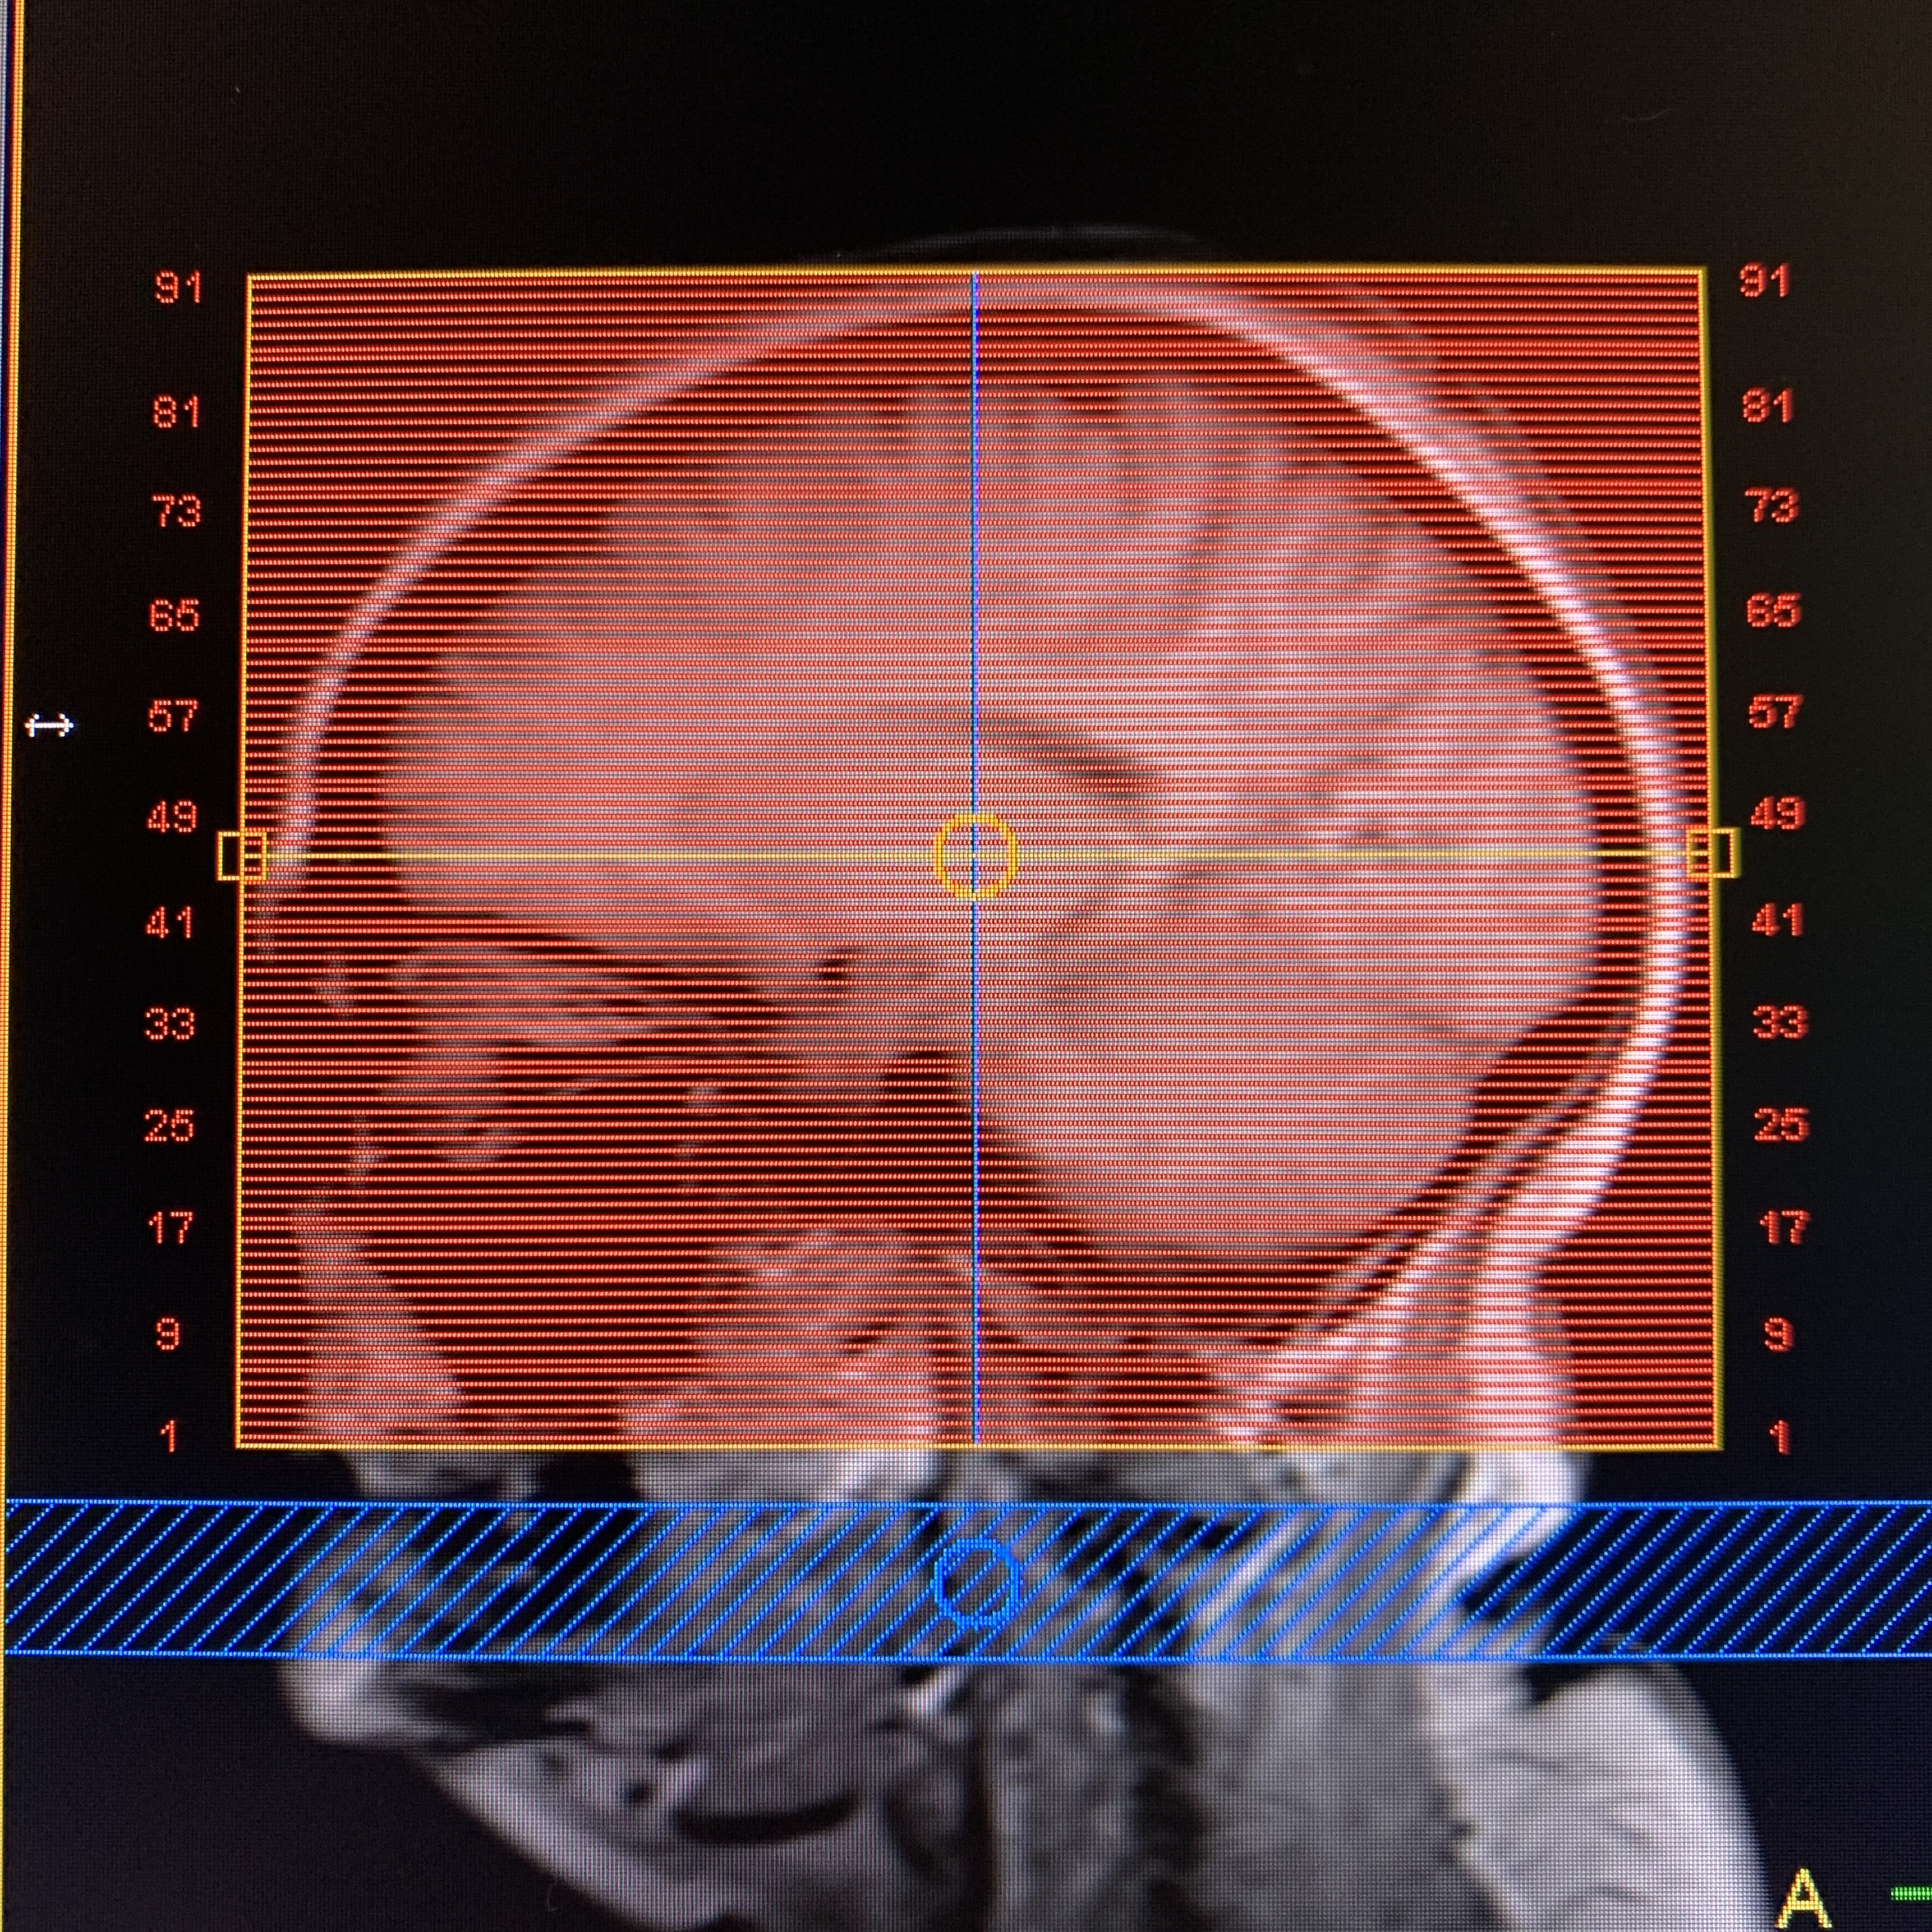

Always acquired in both axial and coronal planes.

“M2D”= Multiple 2D. Multiple single slice acquisition. A number of slices are scanned in sequential order.

| AXIAL | T1 | M2D FFE | 2mm | -0.5mm | None | 23cm | Whole head,vertex to skull base |

| COR | T1 | M2D FFE | 2mm | -0.5mm | None | 23cm | Frontal through occipital, skin to skin |